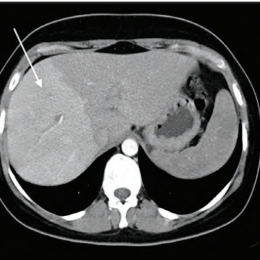

Lymphome de Hodgkin à localisation cutanée spécifique

Un homme de 25 ans consulte pour des symptômes respiratoires incluant une dyspnée, une orthopnée et une toux, accompagnés de l’apparition...